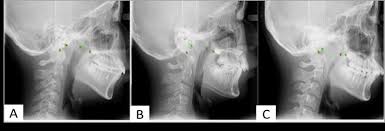

Diş Eti Çekilmesi: Nedenleri, Mekanizmaları ve Önleme Yöntemler Diş eti çekilmesi (gingival retraksiyon), dişeti dokusunun diş kökünden geri çekilmesiyle karakterizedir. Bu durum yalnızca estetik sorun yaratmakla kalmaz, aynı zamanda diş kökünün açığa çıkması nedeniyle hipersensitivite, çürük riski ve periodontal hastalık progresyonu gibi komplikasyonlara yol açabilir. Çekilmenin oluşumunda hem mekanik hem de biyolojik faktörler rol oynar.